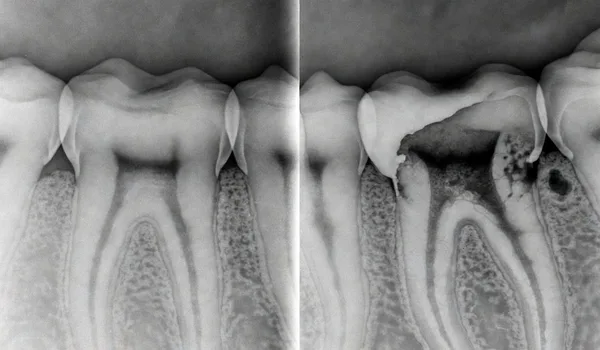

Progression from healthy tooth to cavity to root canal infection

Cavities start small and progress — catch them early to avoid root canal